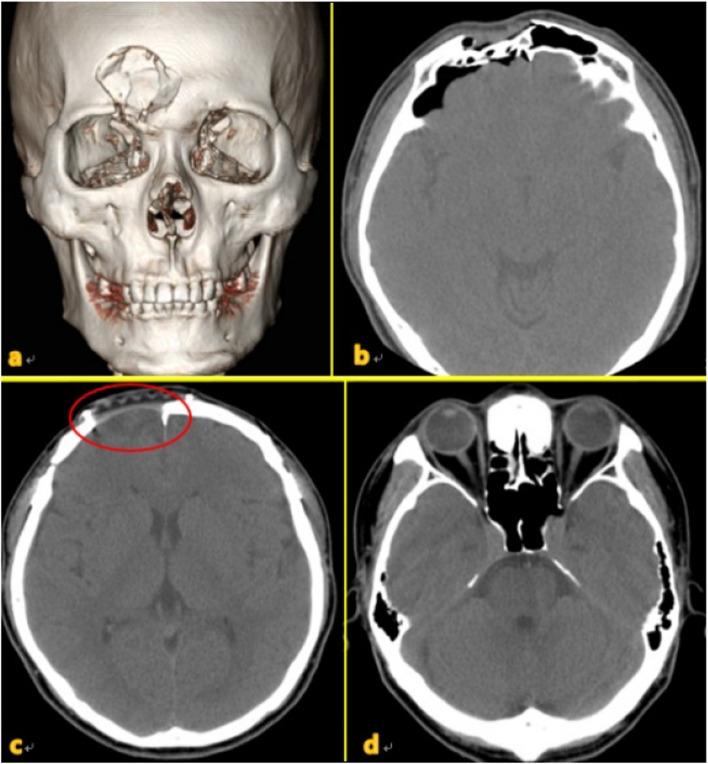

Frontal sinus injuries are relatively rare among facial bone traumas. Without proper treatment, they can lead to fatal intracranial complications, including meningitis or brain abscesses, as well as aesthetic and functional sequelae. The management of frontal sinus injuries remains controversial, with various treatment methods and outcomes being reported. This article describes the clinical characteristics, surgical methods, and outcomes among 17 patients who underwent surgery for frontal sinus injury and related complications.

We retrospectively included 17 patients who underwent surgery for frontal sinus injury and its related complications at the Kangwon National University Hospital between July 2010 and September 2021. Among them, six underwent simple open reduction and fixation of the anterior wall, eight underwent sinus obliteration, and three underwent cranialization. Two patients who underwent sinus obliteration died due to infection-related complications. The patient who underwent cranialization reported experiencing chronic headache and expressed dissatisfaction regarding the esthetic outcomes of the forehead. Except for these three patients, the other patients achieved satisfactory esthetic and functional recovery.